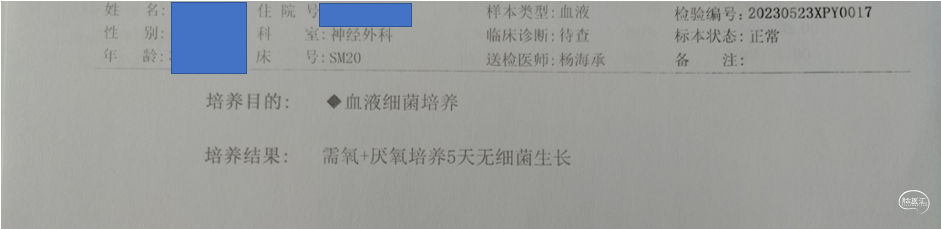

术后化验

2周后停抗生素